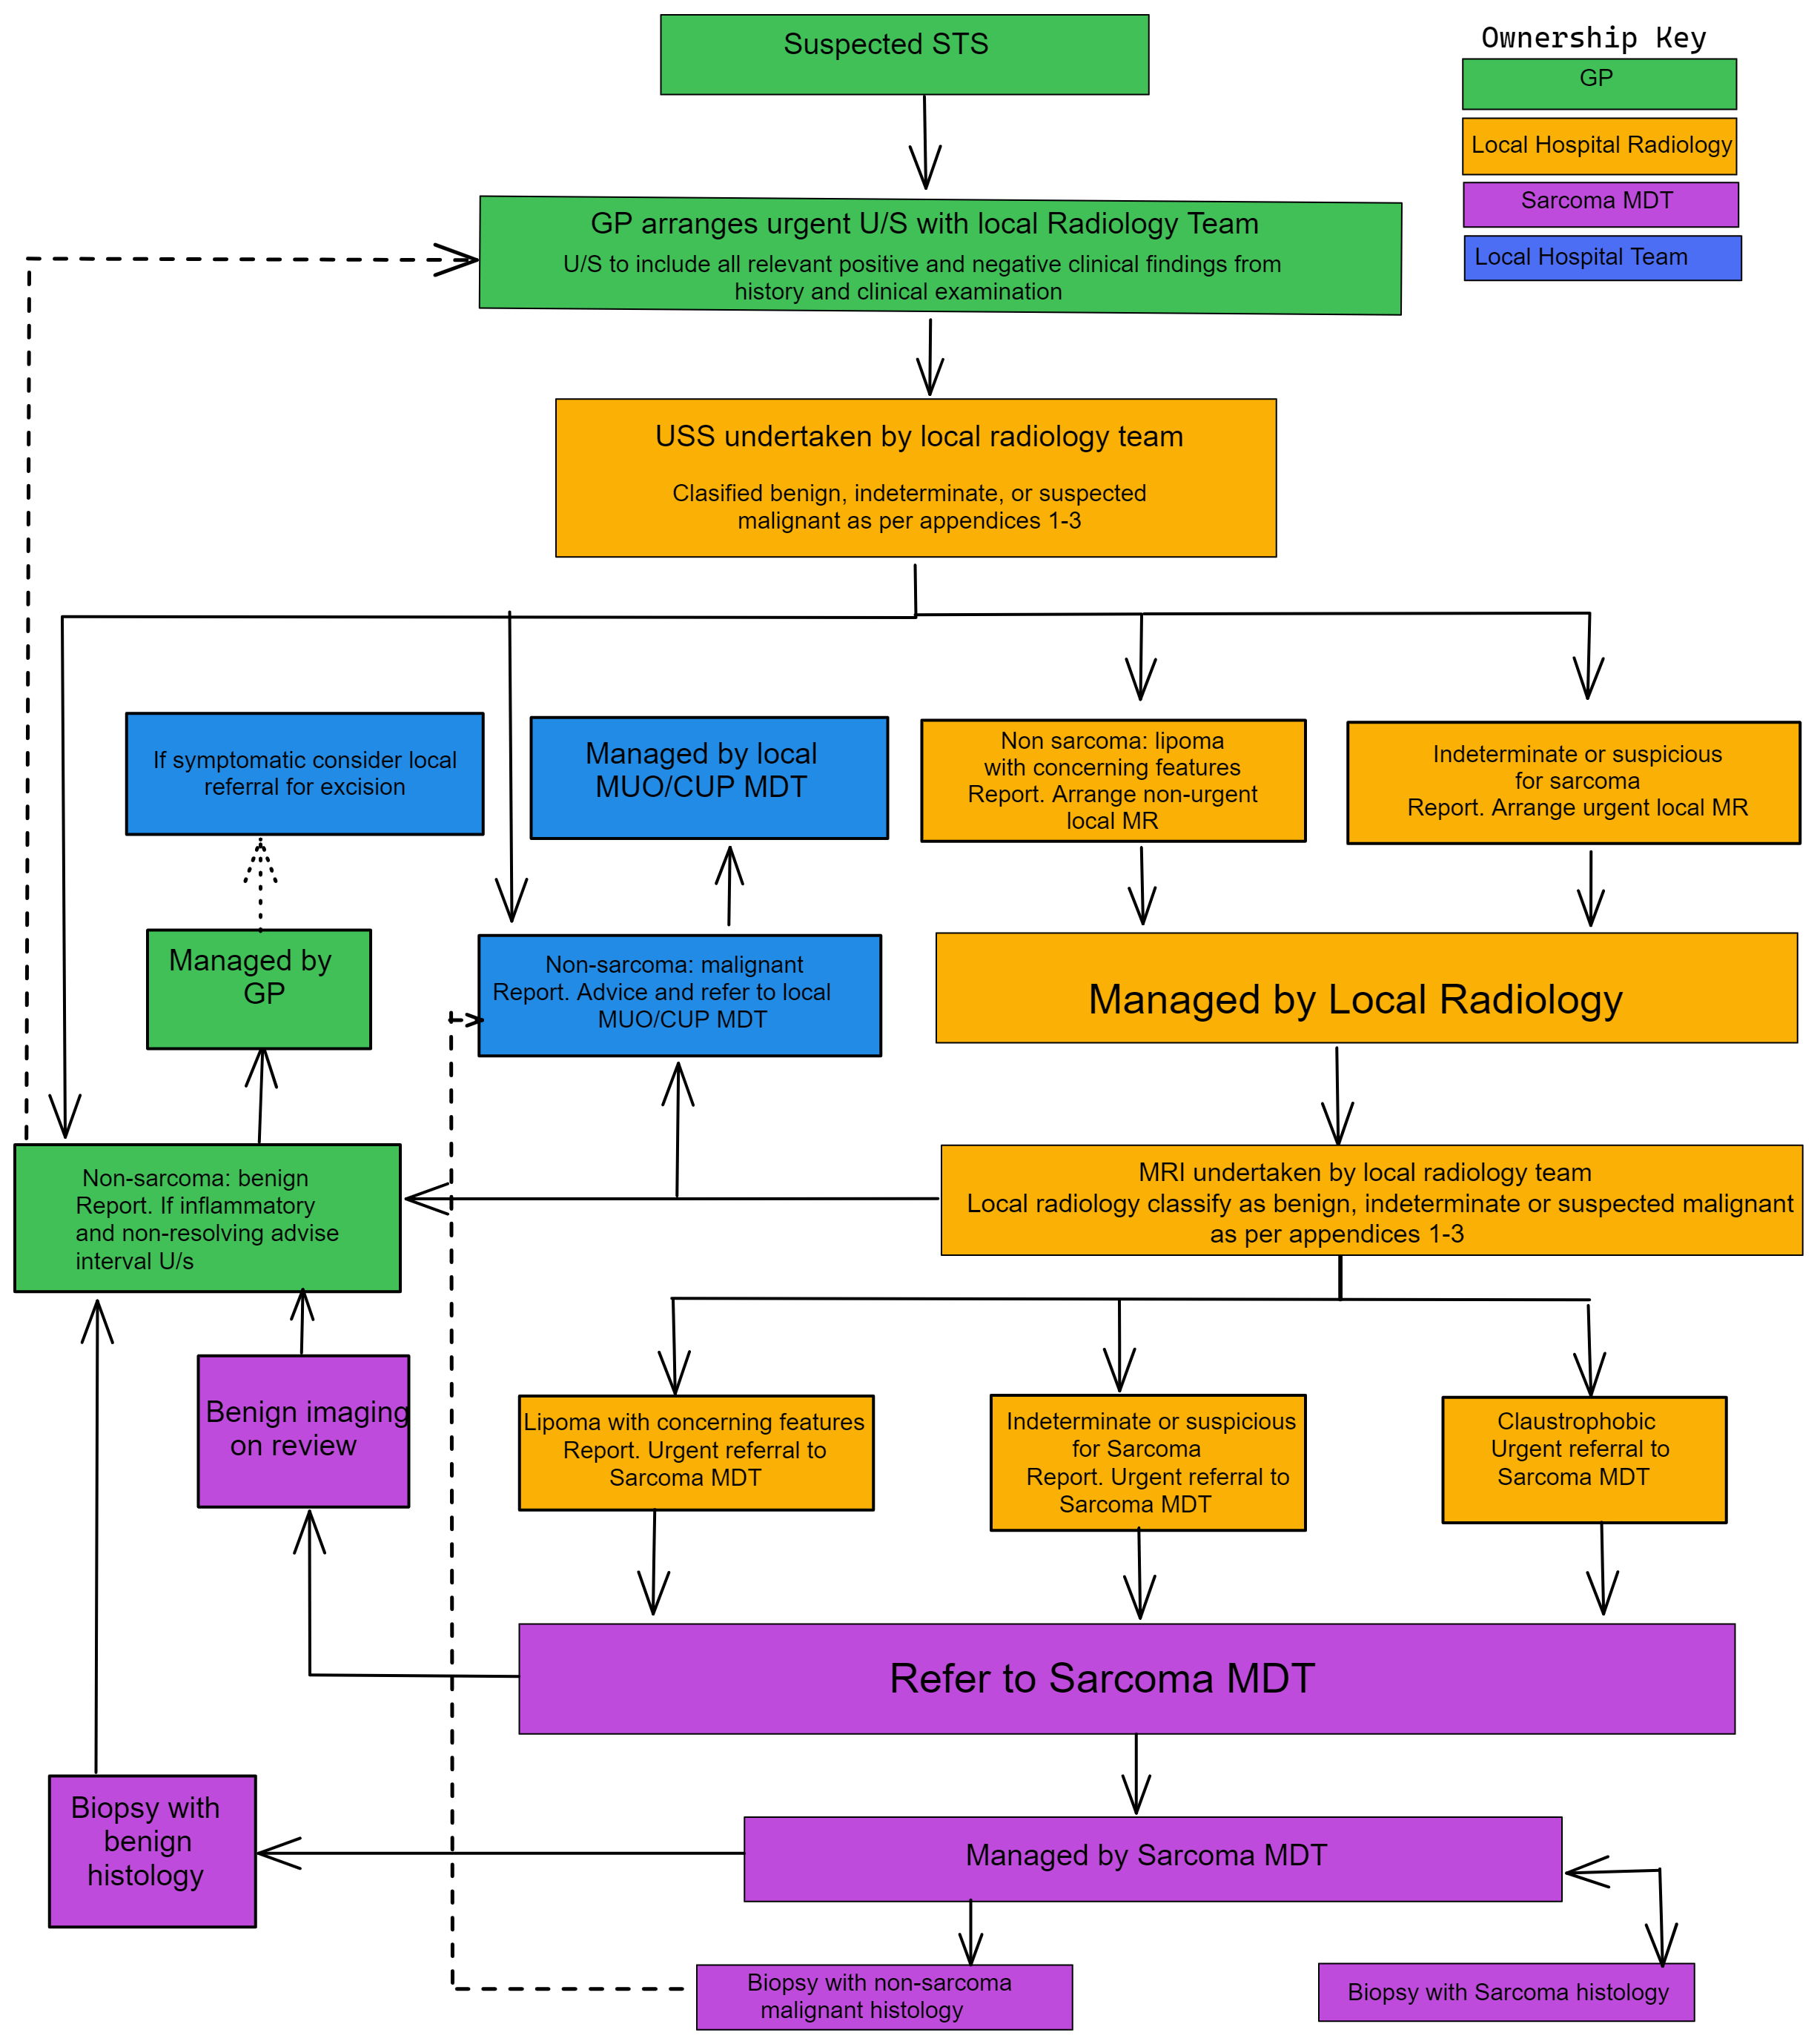

Lipoma Removal Guidelines Infoupdate

https://yorkshireimaging.nhs.uk/images/sarcoma-2-.png